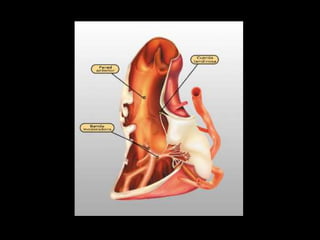

Ambas hojas se unen al nivel del

pedículo vascular formando dos

fondos de saco, que son el seno

transverso (4) de Haller, ubicado

entre los pedículos arterial y

venoso, y el seno oblicuo (5),

situado entre las 4 venas

pulmonares y las venas cavas.

Arteria pulmonar

Saco de theile

Venas pulmonares

izquierdas

Saco de haller

aorta

Vena cava sup

derechas

Vena cava inf